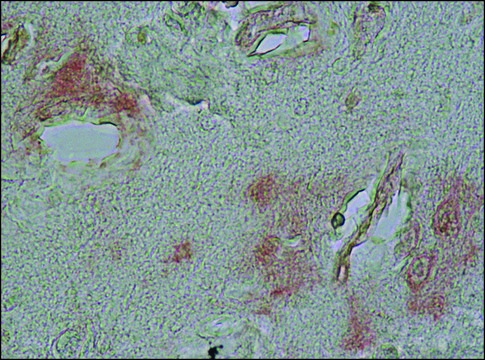

immunohistochemistry (formalin-fixed, paraffin-embedded sections): 1:200 using formic acid treated sections of Alzheimer′s Disease brain, microarray: suitable, western blot: 1:1,000 using extract of rat brain homogenate

兔多克隆抗 α-突触核蛋白抗体用于标记 α-突触核蛋白,通过免疫细胞化学和免疫组织化学 (IHC) 技术(例如免疫印迹)进行检测和定量测定。它还用作探针来确定α-突触核蛋白在阿尔茨海默病(AD)大脑斑块中的存在和作用。